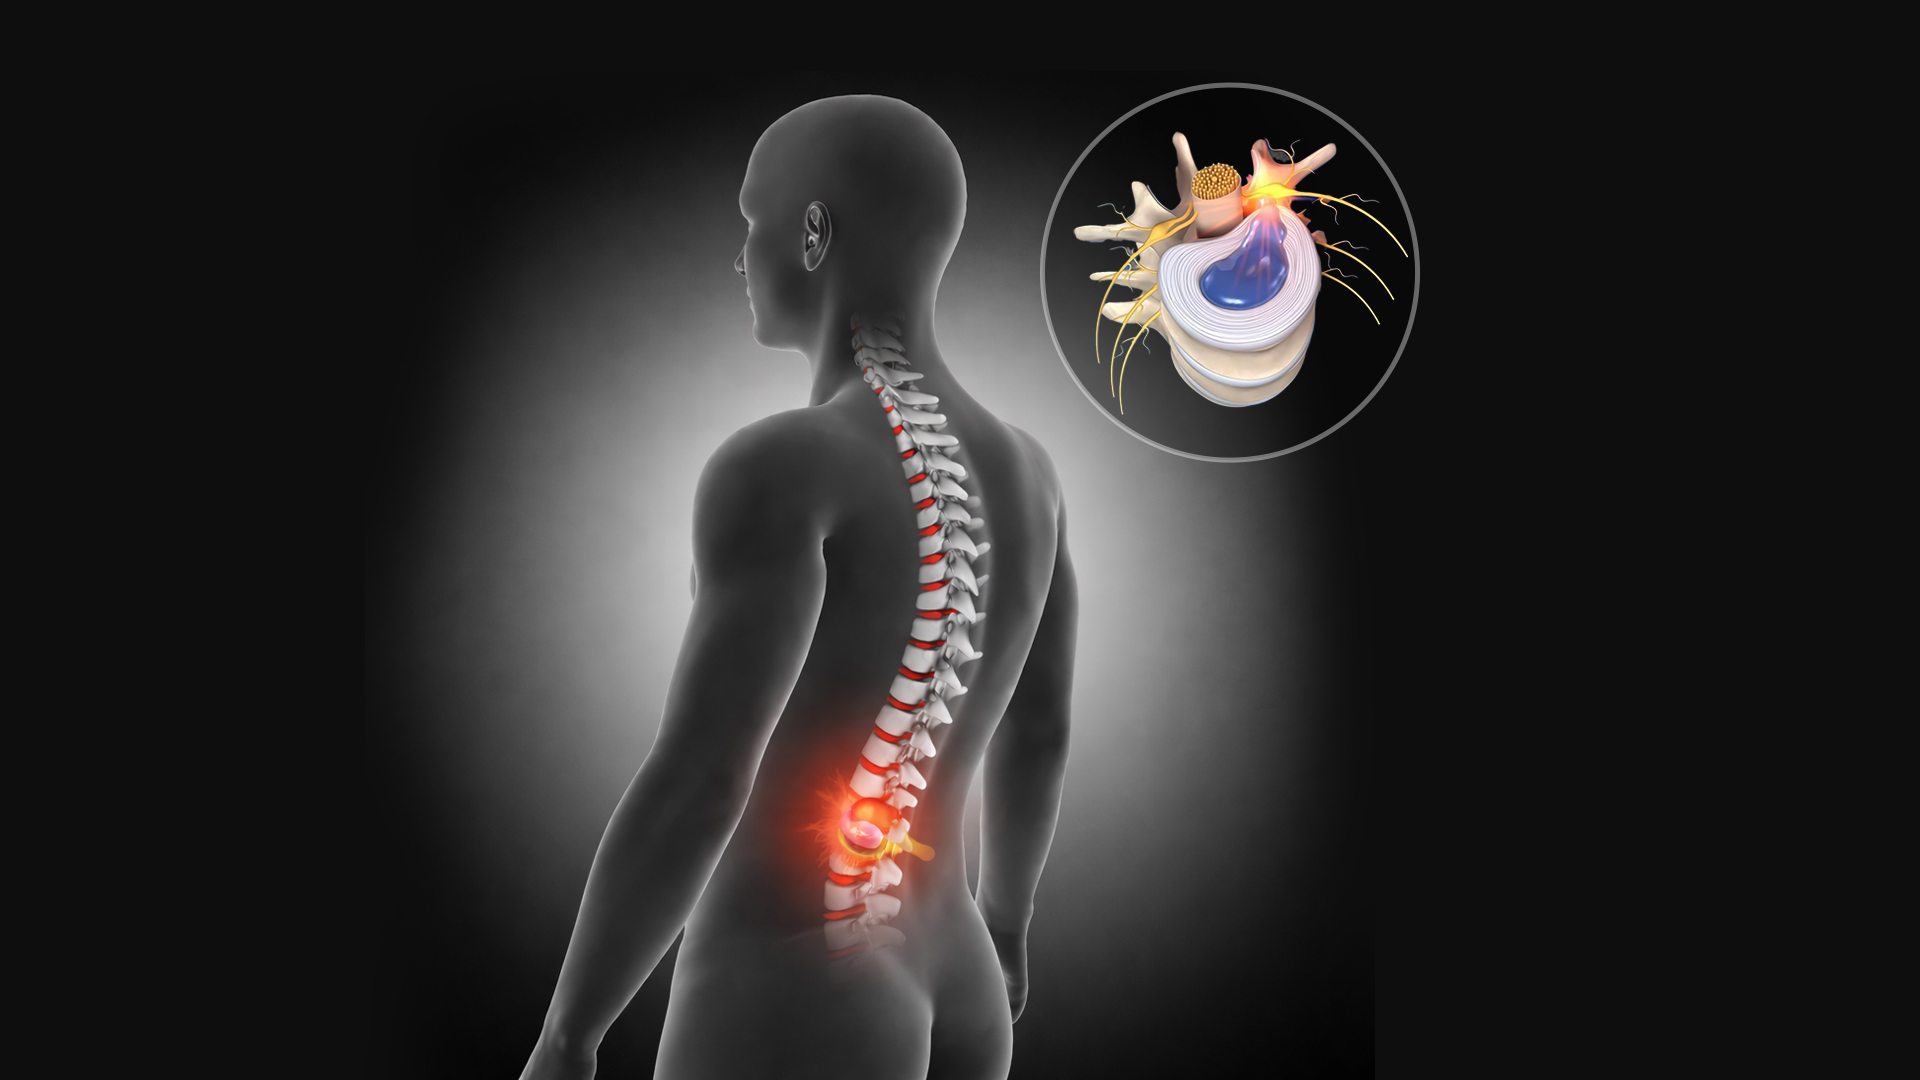

Ce este hernia de disc?

Hernia de disc apare atunci când un disc intervertebral se deplasează și poate comprima o rădăcină nervoasă. Cel mai frecvent afectează zona lombară sau cervicală și este adesea rezultatul dezechilibrelor musculare și al suprasolicitării în timp. Simptome – durere lombară sau cervicală – durere care iradiază pe picior sau braț